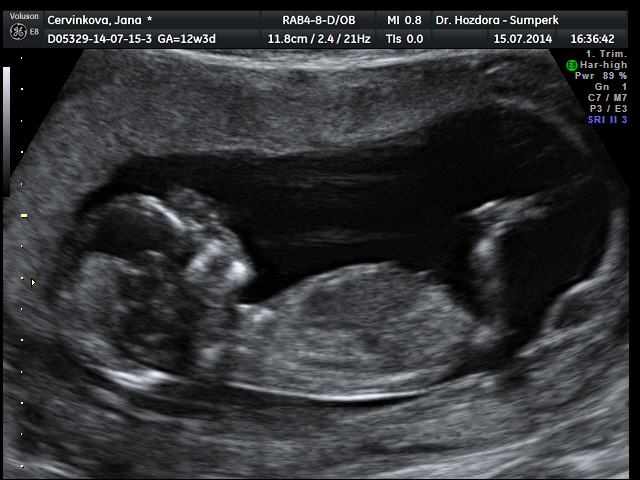

Děvčata srdečně zdravím...genetický ultrazvuk dopadl skvěle.....zítra se dozvím výsledky krevních testů a podle toho se rozhodnu,zda podstoupím nabízenou amniocentézu či ne. Pravděpodobně mám v bříšku holčičku,ale jistější to bude ve 20tt. dostala jsem flešku s obrázkama a kraťoučkým videem,za 3d fotečku jsem si připlatila. Doprovázel mě můj drahoušek a byl z toho docela paf. Mimčo bylo akční.....podle ultrazvuku mám velmi dobrý pocit a věřím,že výsledky budou v pořádku celkově. Jsem tak happy.